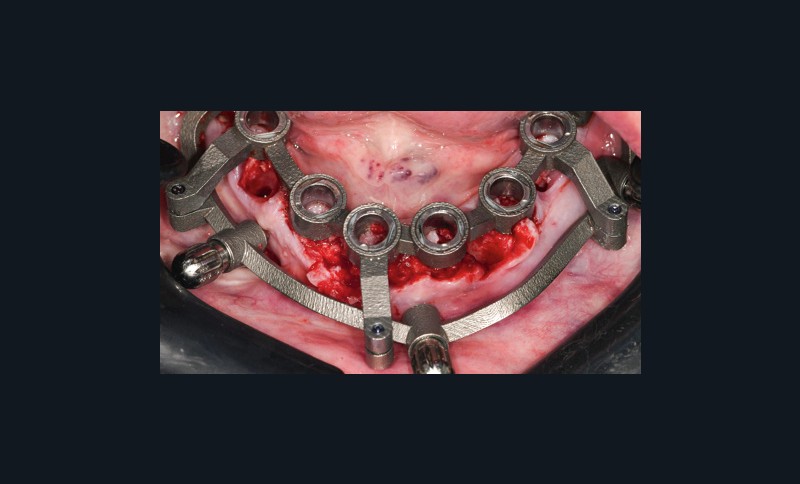

Un premier étage, appelé guide base, est fixé sur le maxillaire à implanter et servira de socle pour les étages supérieurs à empiler (fig. 2). Il doit être aussi rigide que stable pour supporter les contraintes pendant toute la durée de l’intervention : celles du forage implantaire comme celles des poses et déposes des étages supérieurs. Son bon positionnement est donc crucial car il déterminera celui des autres étages. Il peut également servir de repère en fin de procédure, tel un guide de scannage, pour réaliser une empreinte optique (fig. 3). Les appuis sont aussi divers qu’avec un guide statique conventionnel :

- appui osseux : la mise en place nécessite un large lambeau et en fait…